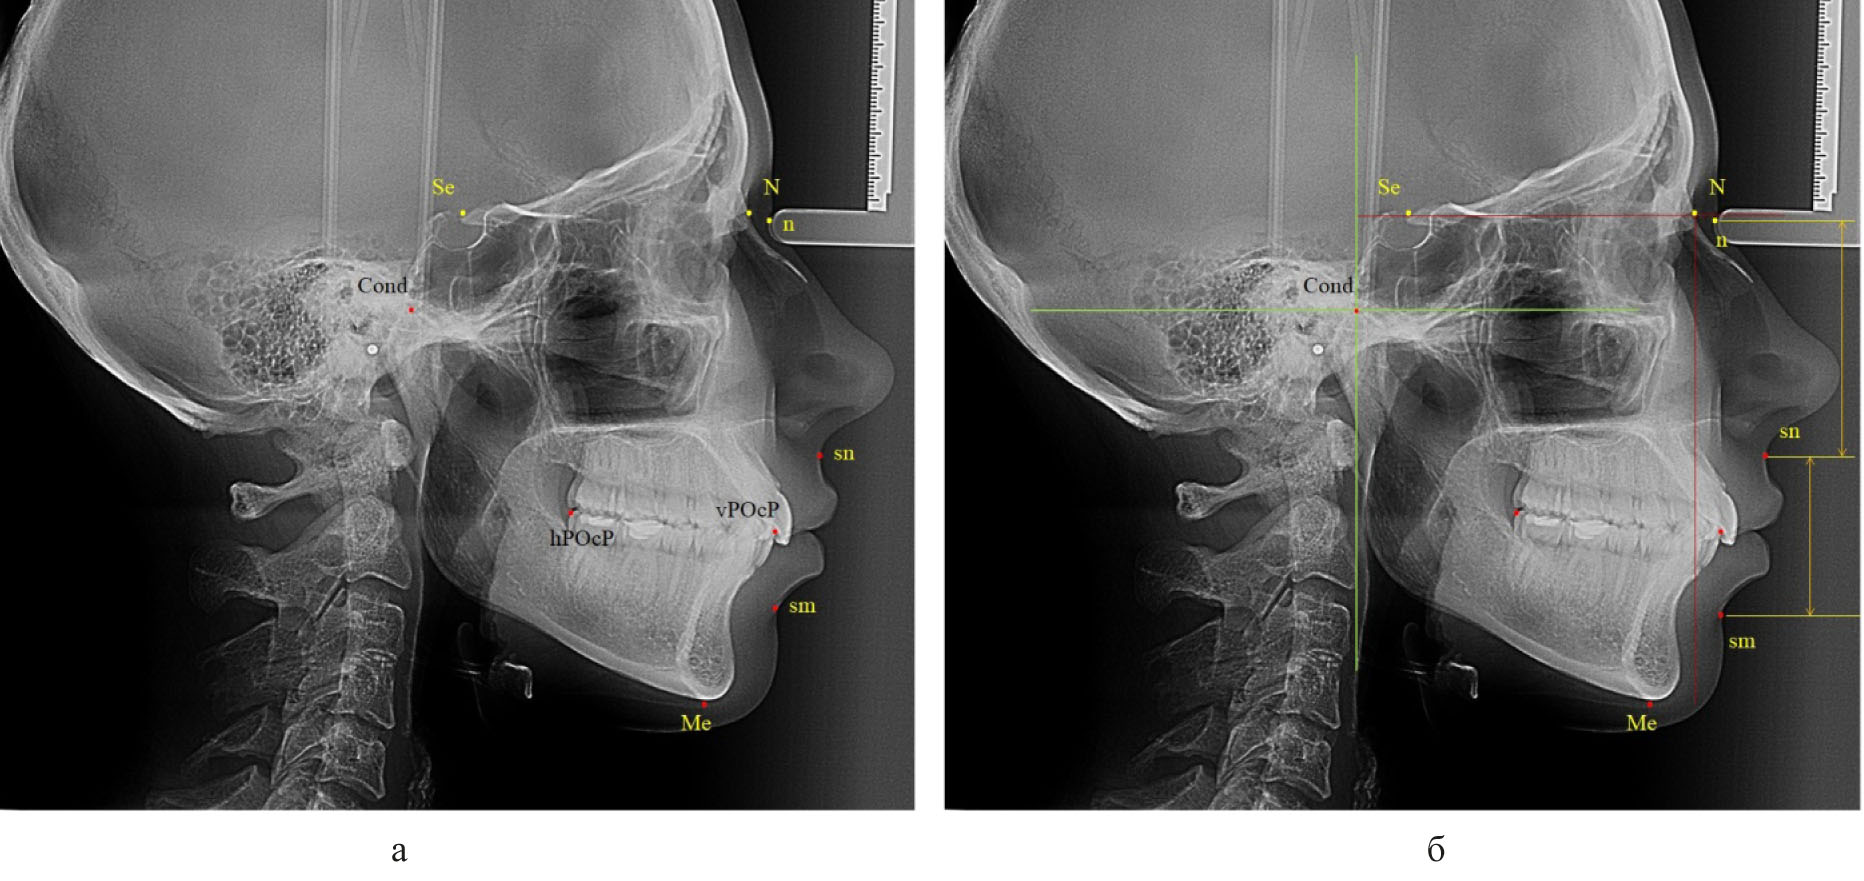

На телерентгенограммах, масштабированных 1 : 1, наносили основные точечные ориентиры. Из многообразия общепринятых в клинической стоматологии точек использовали точки, позволяющие в последующем оценивать вертикальные размеры лицевой области, положение элементов сустава и окклюзионные ориентиры. Для определения положения плоскости основания черепа использовали среднюю точку входа в турецкое седло (Se), которую соединяли с точкой соединения лобной и носовых костей (N), как было рекомендовано A.M. Schwarz (1958). Перпендикулярно к ней из назального костного ориентира опускали линию (прототип вертикали Дрейфуса), которая позволяла определять положение верхней челюсти относительно структур черепа в целом. Кроме этого из костных ориентиров использовали верхнюю точку суставной головки (Cond), заднюю окклюзионную точку (hPOcP), расположенную на дистальном бугорке второго моляра, и переднюю окклюзионную точку (vPOcP) в месте смыкания антагонирующих медиальных резцов. Соединение указанных точек определяло расположение окклюзионной линии (плоскости). Из кожных ориентиров использовали назальную точку (n), субназальный ориентир (sn) и супраментальную кожную точку (sm). Для удобства измерений через указанные кожные точки проводили горизонтальные линии перпендикулярно к вертикали Дрейфуса и измеряли вертикальные размеры лица, в частности «n-sn» и «sn-sm» (рис. 1).

Рис. 1. Некоторые точки (а) и линии (б) для анализа боковой телерентгенограммы

Учитывая вариабельность вертикальных размеров лицевой области, обусловленных типом роста челюстей и лица, после получения абсолютных величин нами оценивались относительные показатели, в частности отношение размеров назального комплекса («n-sn») к межчелюстной вертикали («sn-sm»). Также оценивали положение окклюзионной линии к вертикали Дрейфуса и другим линейным ориентирам, принятым в стоматологии, в частности к Камперовской горизонтали, нижнечелюстной (мандибулярной) линии.